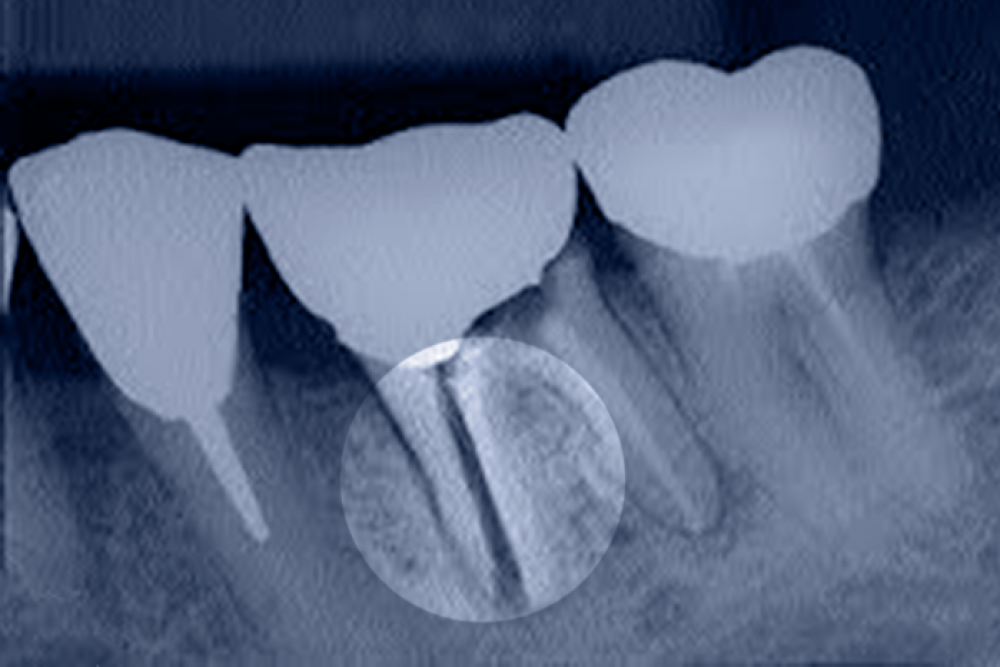

Видалення ретинованого зуба — ефективний спосіб уникнути розвитку негативних наслідків. Діагностика полягає в стоматологічному огляді, прицільній рентгенографії, ортопантомографії, іноді потрібна КТ.

Якщо немає прямих показань для видалення ретинованого ікла, моляра, у зубному ряду є місце, то на початковому етапі проводять хірургічне лікування. Висікають ясна або частину кістки, потім за допомогою брекетів або інших ортодонтичних конструкцій переміщують зуб у правильне положення.